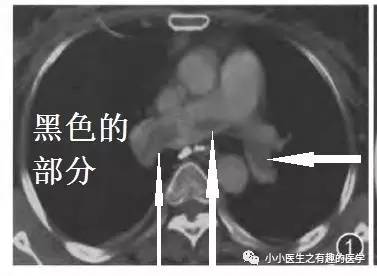

病例一:

女性,老年,胸痛伴气喘20余天。1周前出现双下肢浮肿。查体:双下肢足背浮肿。D-二聚体:5.10 ug/mL。心脏彩超:肺动脉收缩压RVSP:39mmHg。B超:双下肢深静脉血栓形成。

左肺动脉血栓。

左侧血栓,对比右侧就很通畅,一路顺风。